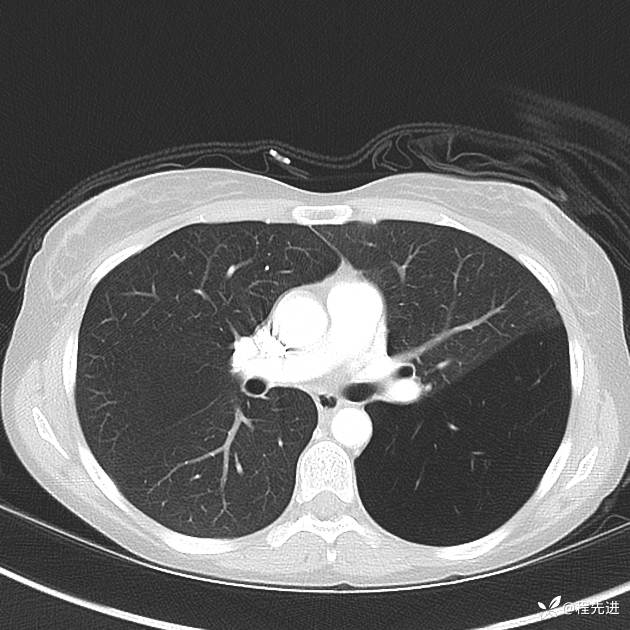

患者性别:女

患者年龄:25岁

简要病史:下胸部疼痛3天

CT增强: